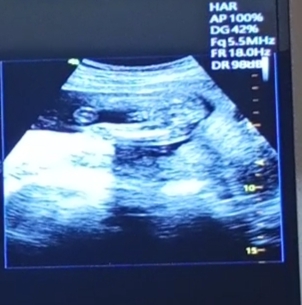

ช่วยดูให้หน่อยนะคะ แบบนี้ผู้หญิงหรือผู้ชายคะ